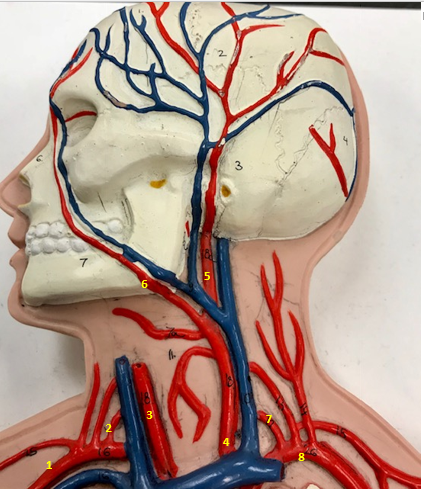

Right subclavian artery

Name #1

Supplies blood to right arm and shoulder

Function of right subclavian artery (1)

Right vertebral artery

Name #2

Supplies blood to brain and spinal cord

Function of right vertebral artery (2)

Right common carotid artery

Name #3

Supplies blood to right neck and head

Function of right common carotid artery (3)

Left common carotid artery

Name #4

Supplies blood to left neck and head

Function of left common carotid artery (4)

Left external carotid artery

Name #5

Supplies blood to face neck and skull

Function left external carotid artery (5)

Left facial artery

Name #6

Supplies blood to face and neck

Function of left facial artery (6)

Left vertebral artery

Name #7

Supplies blood to brain and spinal cord

Function of left vertebral artery (7)

Left subclavian artery

Name #8

Supplies blood to left arm and shoulder

Function of left subclavian artery (8)